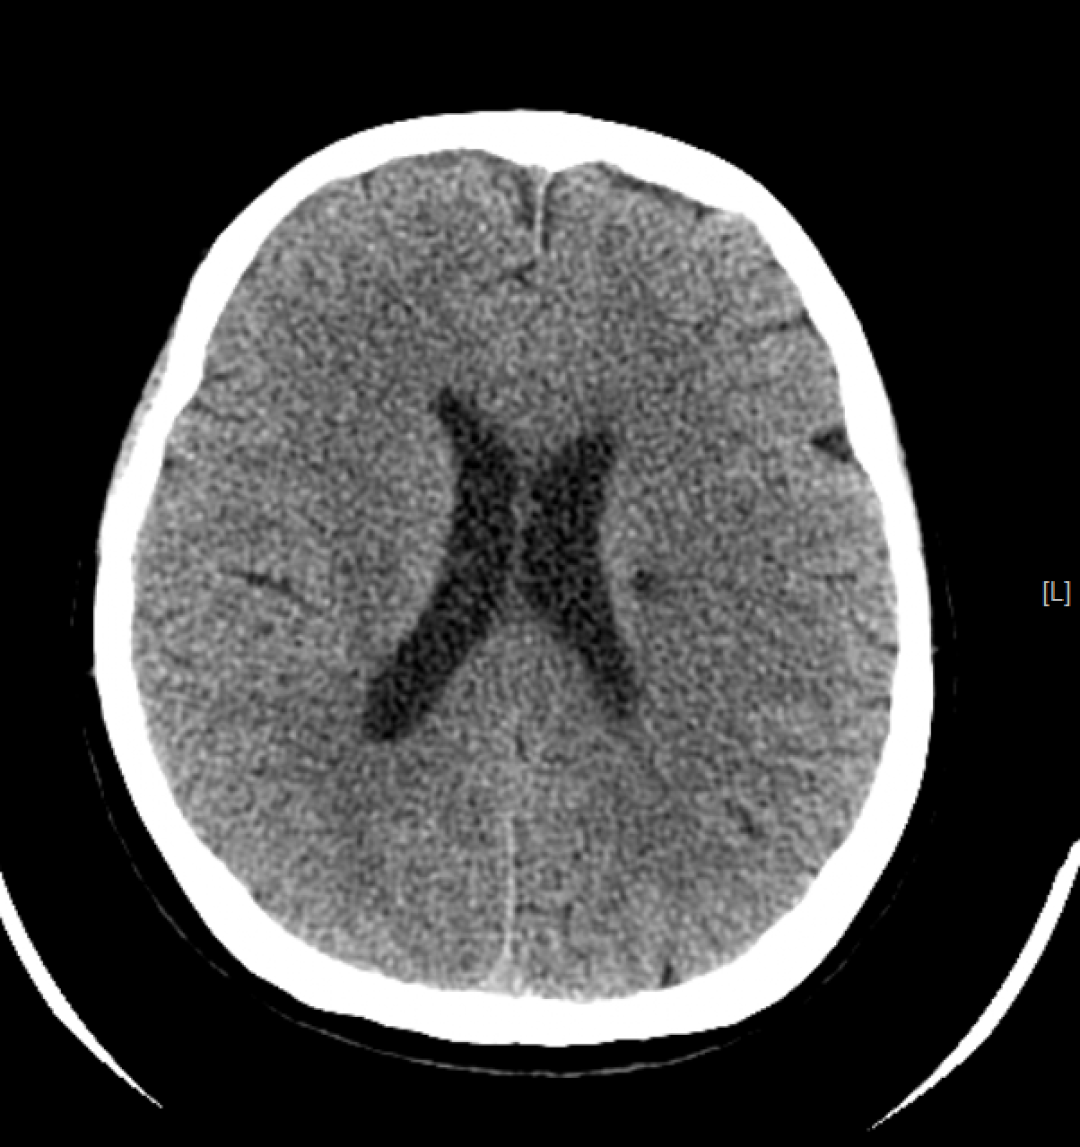

检查应用范围:从头到脚,均可进行CT平扫,主要运用于头颅、颈部、胸部、腹部、脊柱、盆腔、四肢等部位。特别是高分辨率胸部CT,在检查肺部小结节时,运用非常广泛,CT检查脑出血也有相当的优势,另外微小的骨折、大部分器官的病变都能够看到。

CT检查成像原理与DR类似,使用的是X射线,之后通过计算机成像。相较DR,CT可以多角度、多层面、多功能扫描成像,就像把一个面包切成多个平面进行观察。